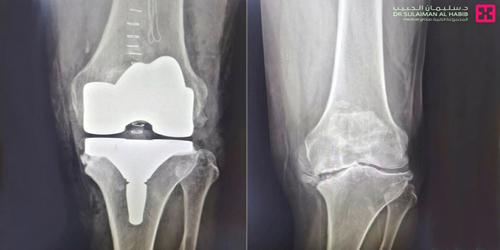

وقال رئيس الفريق الطبي المعالج، إنه فور وصول المريض لعيادة العظام بالمستشفى، تم إخضاعه لعددٍ من التحاليل المخبرية الدقيقة وكذلك فحوصات بالأشعة السينية الرقمية (Digital X-rays) على مفاصل الساقين، وأكدت النتائج وجود زوائد عظمية ناتجة عن الاحتكاك الشديد، وتآكل في مفصلِ الركبة والحاجة الماسة لاستبدالها، وكذلك وجود تقوس شديد بالساقين.

وبعد دراسة التاريخ المرضى جيداً تم وضع خطة علاجية بدأت برفع قياسات الركبتين وتبين أن نسبة التقوس بالساقين هي 25 درجة، بعدها تم الاستعداد للتدخل الجراحي. موضحاً أن العملية استغرقت ساعة ونصف تحت التخدير النصفي، وتمّ فيها استبدال وزارعة مفصل ألماني الصنع من مادة الكوبلات والكروم، والذي يتميز بالجودة والمتانة علاوة على تحقيق المرونة الكاملة للمفاصل والأريحية عند الحركة.